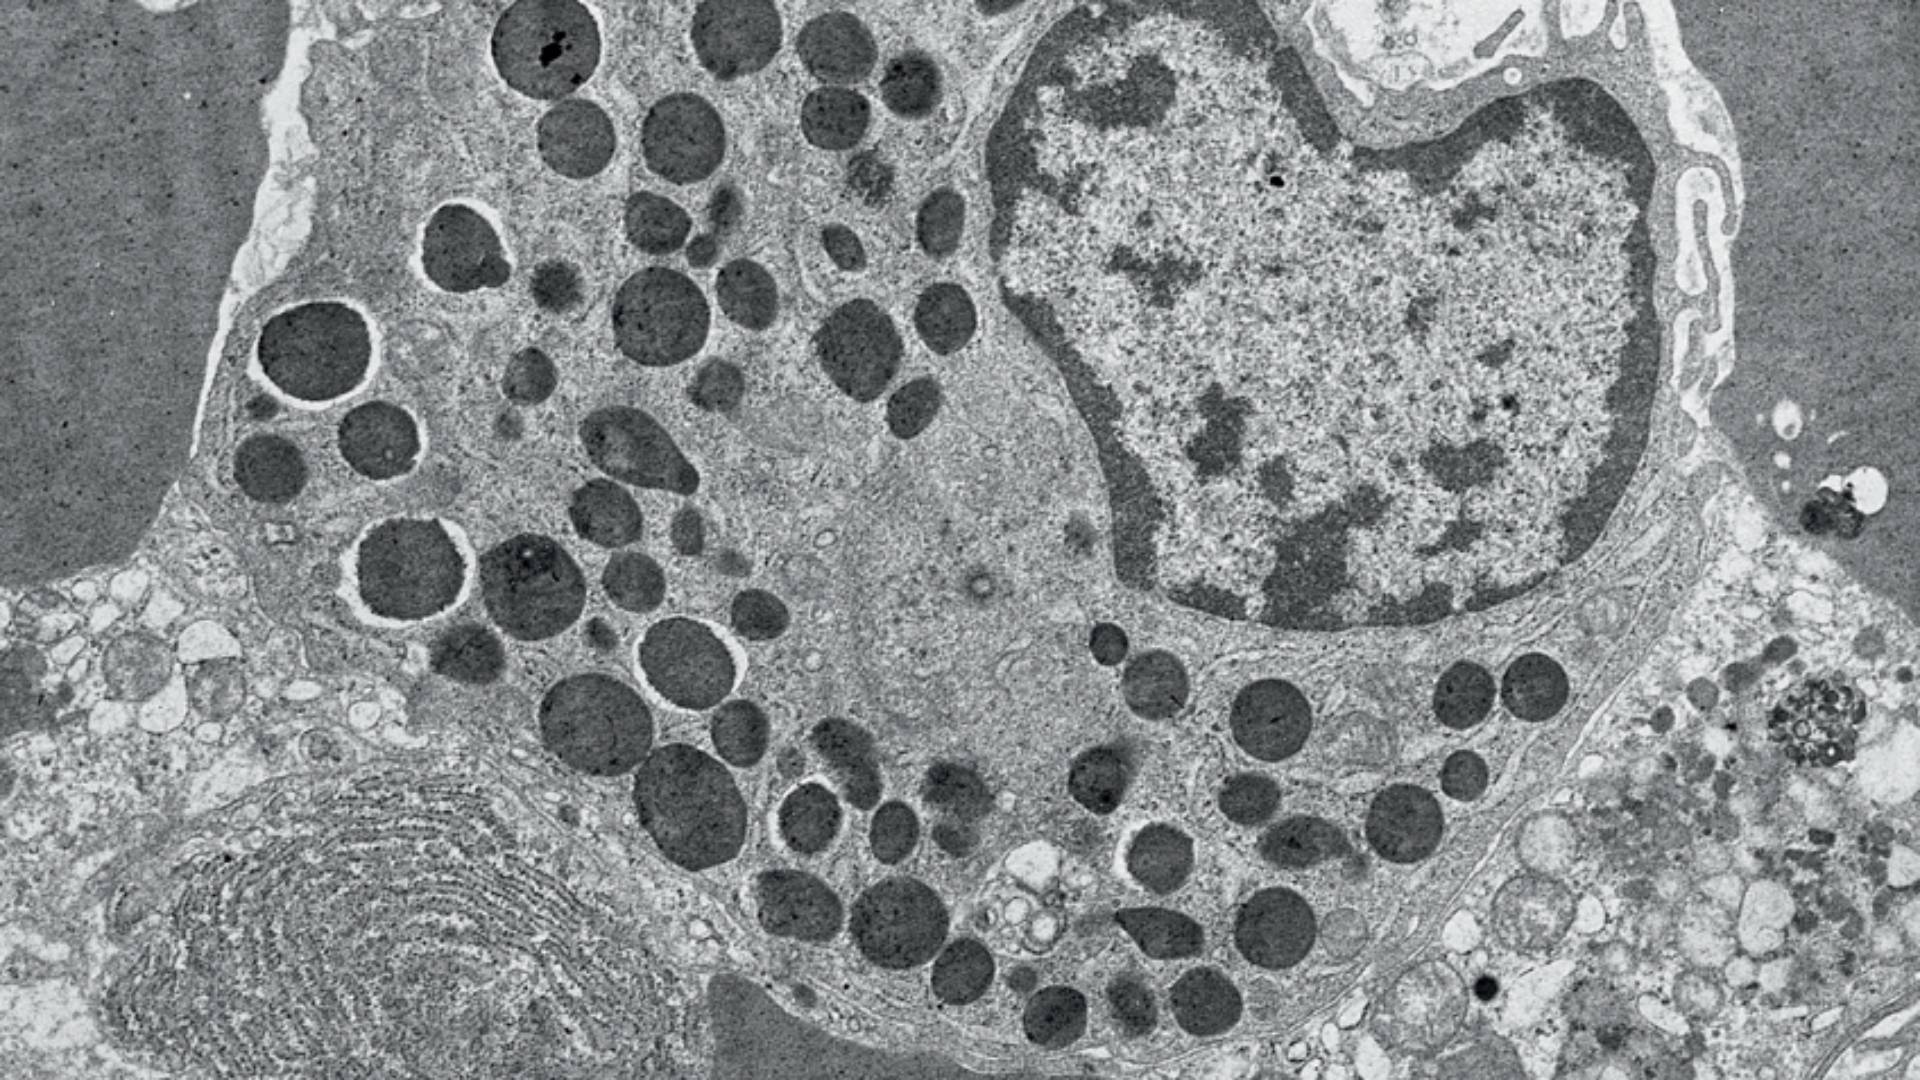

Image d’une cellule basophile montrant les granules (ronds sombres) caractéristiques des granulocytes.

© Inserm/Janine Breton-Gorius